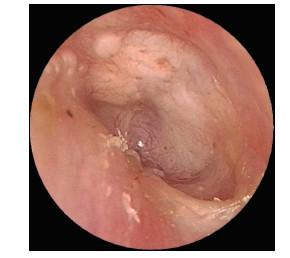

Effect of transauricular endoscopic tympanoplasty in the treatment of large tympanic membrane perforation

DONG Jianfei, DAI Yanhong, CHEN Jie, ZHOU Han, GAO Xia, LU Ling

2023, 21(12): 2014-2017. doi: 10.16766/j.cnki.issn.1674-4152.003279

Abstract:

Objective  To investigate the clinical effect of underlay (medial) tympanoplasty of "external auditory canal flap-tympanic annulus-residual tympanic membrane 360 degree full lift" under oto-endoscope for the treatment of large tympanic membrane perforation, and to introduce the key points and techniques of clinical surgery.  Methods  Thirty patients (30 ears) with large tympanic membrane perforation who underwent tympanoplasty at Nanjing Drum Tower Hospital from July 2019 to December 2021 were selected. They were divided into groups according to the type of surgery. In the observation group, 15 patients (15 ears) underwent tympanoplasty by underlay (medial) tympanoplasty after the external auditory canal flap, drum ring and residual tympanic membrane were completely opened under oto-endoscope. In the control group, 15 cases (15 ears) underwent underlay (medial) tympanoplasty after 270-degree elevation of the external auditory canal posterior wall flap, tympanic ring and residual tympanic membrane under oto-endoscope. Postoperative follow-up was conducted for 6 months, and operative time, blood loss, tympanic healing and postoperative hearing were compared between the two groups.  Results  The mean operating times of the observation group and the control group were (108.33±8.28) min and (111.00±12.96) min, respectively, with no statistical significance. The mean blood loss were (13.00±3.00) mL and (12.07±3.31) mL, respectively, and the difference was not statistically significant. The success rate of tympanic membrane repair at 6 months was 100.00% (15/15) in the observation group and 86.67% (13/15) in the control group. There were 12 cases (80.00%) of hearing improvement in the observation group and 9 cases (60.00%) in the control group, however, the difference was not statistically significant (P>0.05).  Conclusion  Compared to conventional tympanoplasty with underlay (medial) tympanoplasty after 270 degrees of external ear canal flap, tympanic annulus and residual tympanic membrane under oto-endoscope, tympanoplasty with underlay (medial) tympanoplasty after 360 degrees of full flap, tympanic annulus and residual tympanic membrane and residual tympanoplasty under oto-endoscope has the same advantages in the treatment of large tympanic membrane perforation, but it can improve the success rate of repair and postoperative hearing of patients.